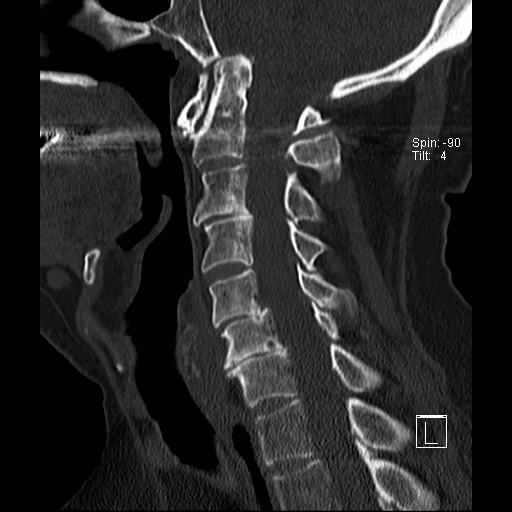

Lồng nền sọ

Lồng nền sọ, còn gọi là sụt lún sọ não hay ấn nền sọ, xảy ra ở 5-10% bệnh nhân viêm khớp dạng thấp cột sống cổ.

Trong lồng nền sọ, mỏm răng sa vào lỗ chẩm làm thu hẹp không gian dành cho tủy sống.

Biểu hiện lâm sàng đa dạng, từ đau đầu mạn tính, hạn chế vận động cổ đến suy giảm thần kinh cấp tính (chèn ép tủy sống và thân não, có thể dẫn đến liệt hoặc thậm chí tử vong nếu cổ bị di chuyển ở một số tư thế nhất định).

Hình ảnh

Cuộn xem các lát cắt CT.

Có hình ảnh di chuyển lên trên của mỏm răng vào lỗ chẩm.